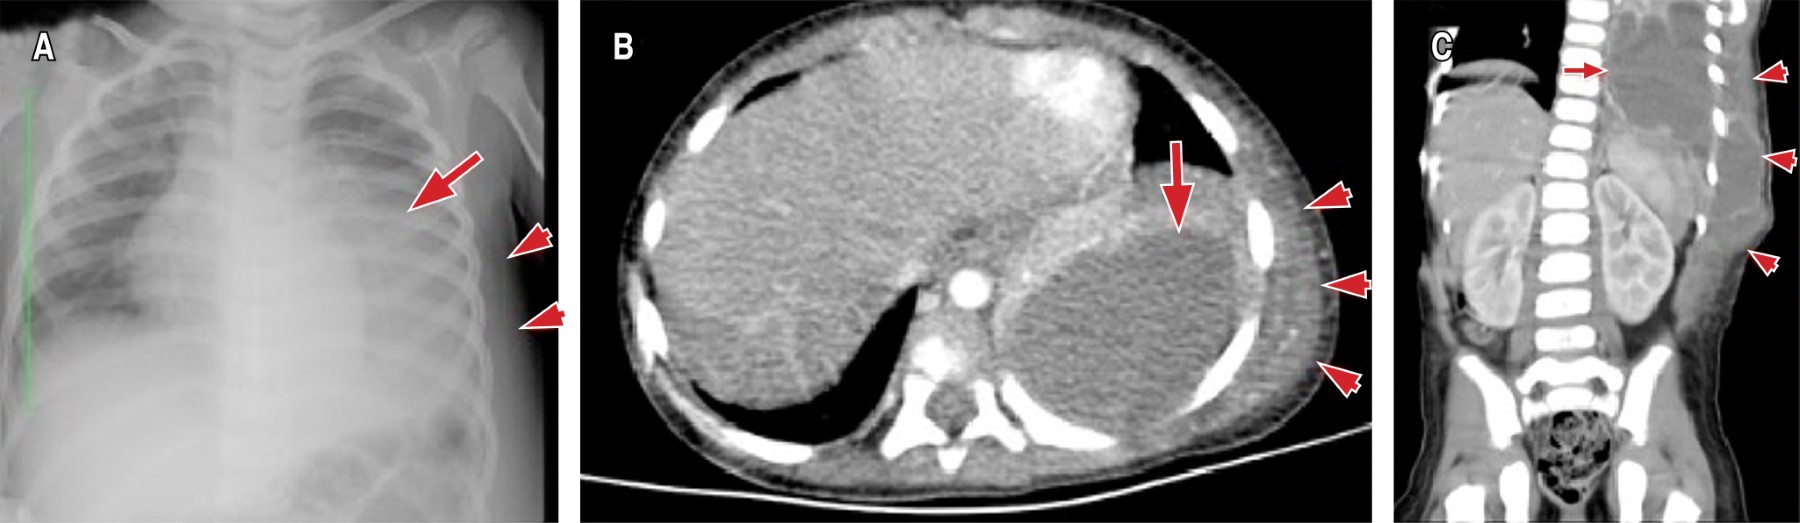

Por ecografía, la masa toracoabdominal era de apariencia líquida, heterogénea, tabicada, de bordes irregulares, sugestiva de colección de partes blandas, además se identificó derrame pleural izquierdo, con contenido particulado, que estaba adyacente a la colección. Por su parte, en la radiografía de tórax se observó opacidad de la mitad inferior del pulmón izquierdo -sugestivo de derrame pleural-, y engrosamiento de los tejidos blandos del hemitórax (Figura 1A). Mientras que en la tomografía de tórax contrastada (Figura 1B y 1C) se delimitó una colección pleural tabicada, de pared gruesa, ubicada en tercio inferior del hemitórax izquierdo, la cual tenía comunicación a tejidos blandos de la pared toracoabdominal del mismo lado. No se identificaron lesiones líticas en la pared costal. Con los hallazgos, se integró el diagnóstico de empiema necessitatis, iniciando manejo antimicrobiano empírico con oxacilina y clindamicina.

Figura 1